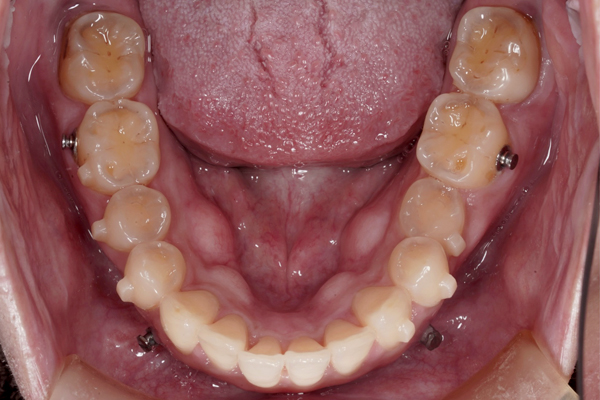

本治療では、インビザラインを用いた非抜歯矯正を行っています。治療の進行にあわせて、インプラントアンカーを使用し、歯を後方へ移動させる計画です。治療期間はおよそ1年6か月を予定しており、現在は開始から9か月が経過した段階です。

上の歯の比較(咬合面)

下の歯の比較(咬合面)

現在、治療開始から9ヶ月が経ちました。

マウスピース矯正は患者さまの使用頻度によって治療の成績が大きく変わってしまいます。マウスピース以外にゴムを使用しています。患者さまは真面目に矯正治療に取り組んでいただいています。このまま最後まで頑張っていきましょう。